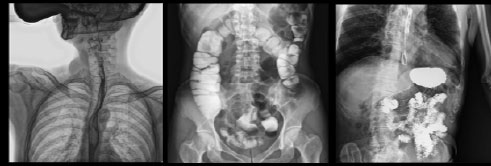

- Применяется в различных клинических рентгенологических исследованиях, таких как рентгенография, цифровая флюороскопия, контрастная и визуализированная точная съемка DR

Рентгенологические исследования: рентгенография больших переломов костей и масштабное физическое рентгенографическое обследование, флюороскопия всех частей тела (грудная клетка, живот и т.д.), пищеводная ангиография, ангиография верхних отделов желудочно-кишечного тракта, полная ангиография желудочно-кишечного тракта, холангиография, Т-образная холангиография, ЭРХПГ, внутривенная пиелография, гистеросальпингография и т.д.